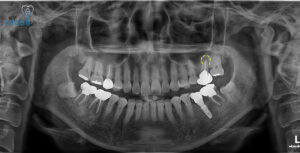

자세히 확인을 하기 위해

파노라마 촬영을 해보았는데요.

해당 치아 뿌리 끝에

염증이 크게 잡혀있는 것을

확인할 수 있었어요.

이러한 상태는

단순한 잇몸 질환이 아니라

치아 뿌리 깊은 곳에서 비롯된 문제로,

치근낭종이 동반될 가능성도 있기 때문에

적절한 치료가 반드시 필요했어요.